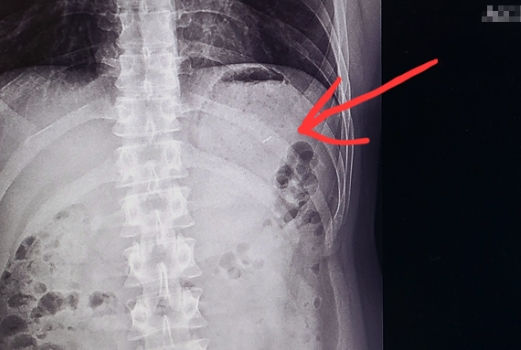

본 사건에서는 심지어 제보자가 엑스레이를 찍으러갔는데 뱃속에서 주사바늘 조각이 그대로 노출되면서 더욱 충격을 주었는데요.

엑스레이 결과 충격적이게도 “같이먹은 저는 이상없고 남편 위장에 바늘조각으로 추정되는 이물이 나왔다”라며

“주말이고 응급실이라 내시경이안되서 평일외래방문해서 경과 보자고 하셨다”라고 전했는데요. 🤦♂️

제보자가 공개한 사진 엑스레이에서는 뱃속에 있는 바늘조각이 그대로 보이는 상태여서 충격을 주었는데요.